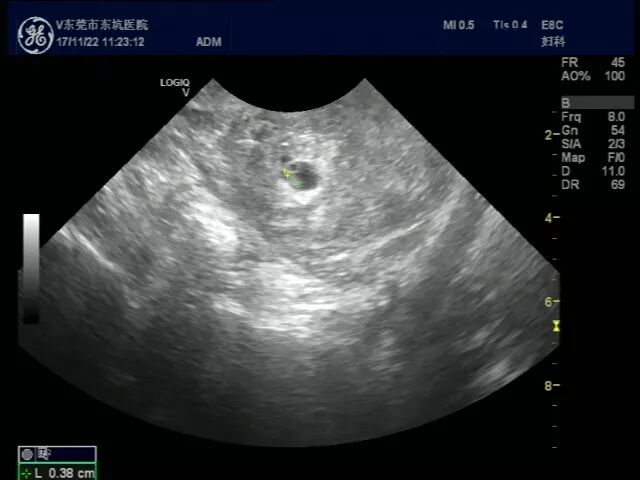

经过周主任的检查以及我院B超的详细排查,发现张小姐不仅是宫内怀孕了,宫外居然也怀孕了,周萍主任也表示在大医院从医这么多年,自然怀孕下,宫内外同时怀孕非常罕见,同时,还出现了宫外孕引起的腹腔内大出血。

宫内怀孕B超图           宫外怀孕B超